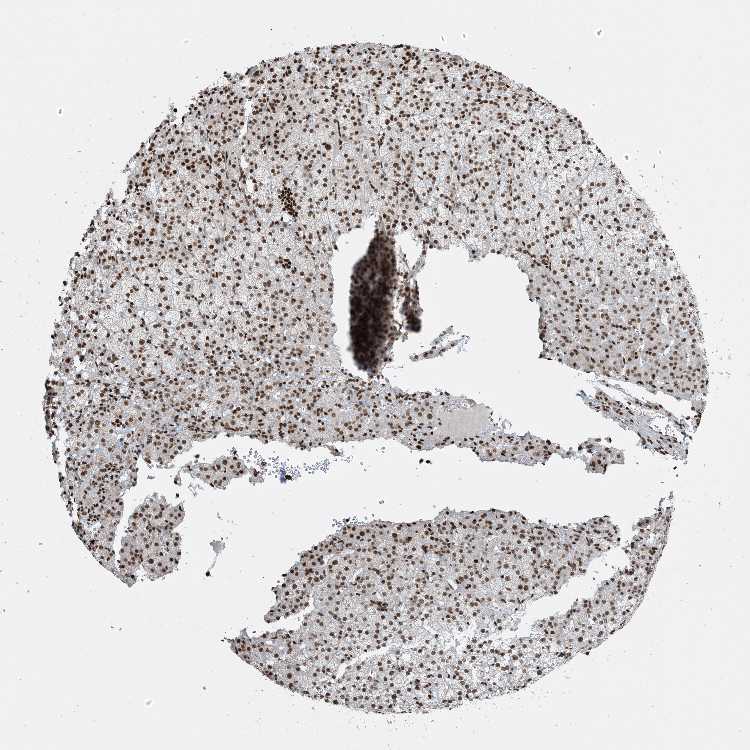

ADRENAL GLAND - Antibody stainingi

Antibody staining in the annotated cell types in the current human tissue is reported as not detected, low, medium, or high, based on conventional immunohistochemistry profiling in selected tissues. This score is based on the combination of the staining intensity and fraction of stained cells.

Each image is clickable and will lead to virtual microscopy that enables deeper exploration of all samples and also displays staining intensity scores, fraction scores and subcellular localization as well as patient and tissue information for each sample.

Antibody HPA042570Antibody CAB037166Antibody CAB037187Antibody CAB037221

Glandular cells HighMediumMediumMedium